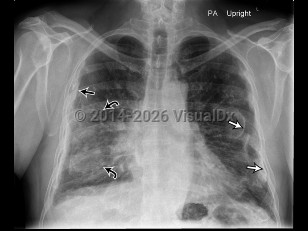

Asbestosis

Asbestosis is a fibrotic lung disease resulting from extensive inhalation of asbestos fibers. Symptoms include insidious onset of cough, dyspnea, and chest discomfort. Pleural effusions and mesothelioma are associated disorders. Latency between exposure to asbestos and development of disease is typically at least 20 years, making diagnosis difficult.